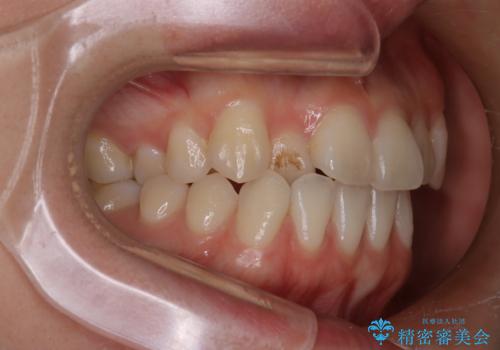

八重歯と前歯の逆の咬み合わせを、目立たない矯正で同時に改善

- 八重歯と、右上前歯(2番)が下の歯より内側に入っている反対咬合を気にされてご来院されました。精密な検査の結果、八重歯と反対咬合を同時に改善するためには、歯列全体にスペースを確保する必要があると判明。患者様のご希望から、透明で目立たないインビザライン(マウスピース矯正)による治療計画を立案しました。奥歯全体を奥へ動かす遠心移動でスペースを作り、これらの複雑な問題を一括で解消することを目指します。

今回の矯正治療では、透明なマウスピース型の装置インビザラインを使用しました。治療は、緻密なデジタル計画に基づき、奥歯から順に歯列全体を後方へ移動させる遠心移動を実施。これにより、八重歯を正しい位置に並べるためのスペースを確保しました。同時に、右上の2番を前方に誘導することで反対咬合を解消。結果として、抜歯することなく八重歯と反対咬合という複数の問題が改善され、機能的で美しい歯並びを獲得していただけました。